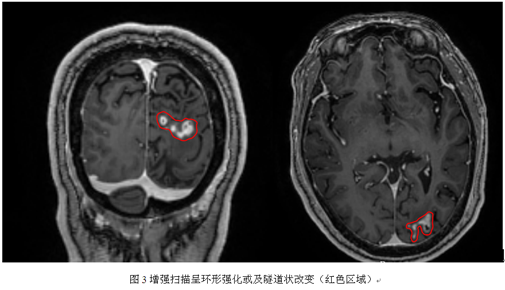

入院查体:神经系统检查未及明显阳性体征。头部CT示:左枕局部可见钙化影(如图1),左侧额顶枕多发软化灶(CT表现为低密度灶,如图2)。头颅MRI增强扫描后显示:1.左侧额顶枕叶及左侧基底节区多发病变,现增强后左侧枕叶病变异常强化,考虑存在寄生虫感染(脑裂头蚴病可能)2.脑白质少许脱髓鞘灶;3.脑干偏左侧缩小,考虑沃勒变性。血/脑脊液化验示寄生虫抗体IgG/IgM:阳性。

2.MR扫描:汪文胜等报道一组25例病例影像学特征:1.T1W1呈低信号,T2W2呈稍高或等信号,冠冠状位和矢状位增强图像呈更清楚的梭形或柱形隧道样改变——“隧道征”;2.聚集的小环状或串珠样强化;3.不同阶段的病灶交替出现在同一层面的图像上;4.病灶具有游走性。人体感染脑裂头蚴病后,裂头蚴幼虫会在脑组织内穿行,造成坏死隧道,虫体内的蛋白酶能溶解周围组织,引起炎症反应这就是形成脑裂头蚴病影像学表现的病理学基础,即机械性损伤与炎性肉芽肿并存。